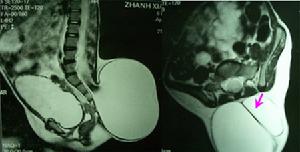

3.其他症狀少數脊膜膨出向椎管側方或咽後壁、胸腔、腹腔及盆腔內伸展者可表現膨出囊壓迫鄰近組織器官的症狀一部分脊膜膨出患兒合併腦積水和脊柱側彎等其他畸形,可出現相應的症狀。

2.CT、MRI掃描顯示脊柱裂及脊髓、神經的畸形,以及局部粘連等病理情況。

MRI檢查:能顯示囊內的脊髓和神經根並能發現突出常伴有的其它畸形如脊髓栓系椎管內或皮下脂肪瘤皮樣囊腫或表皮樣囊腫等。